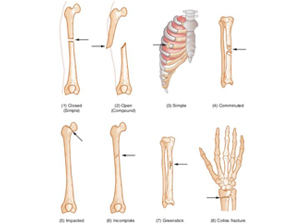

There are several different ways in which a bone can fracture; for example a clean break to the bone that does not damage surrounding tissue or tear through the skin is known as a closed fracture or a simple fracture. On the other hand, one that damages surrounding skin or tissue is known as a compound fracture or an open fracture. Compound or open fractures are generally more serious than simple fractures, with a much higher risk of infection.

A fracture, also referred to as a Bone fracture, FRX,FX, Fx or #, is a medical condition where the continuity of the bone is broken. There are several different ways in which a bone can fracture; for example a clean break to the bone that does not damage surrounding tissue or tear through the skin is known as a closed fracture or a simple fracture. On the other hand, one that damages surrounding skin or tissue is known as a compound fracture or an open fracture. Compound or open fractures are generally more serious than simple fractures, with a much higher risk of infection.

There are several different ways in which a bone can fracture; for example a clean break to the bone that does not damage surrounding tissue or tear through the skin is known as a closed fracture or a simple fracture. On the other hand, one that damages surrounding skin or tissue is known as a compound fracture or an open fracture. Compound or open fractures are generally more serious than simple fractures, with a much higher risk of infection.  The period immediately after a bone fracture is critical for the proper repair of the bone and healing of the affected tissues. Bones begin to heal very quickly after a fracture and the bone tissue will knit together with any nearby bone fragments to form a callus of cartilage and eventually new bone tissue.

A fracture, also referred to as a Bone fracture, FRX,FX, Fx or #, is a medical condition where the continuity of the bone is broken. There are several different ways in which a bone can fracture; for example a clean break to the bone that does not damage surrounding tissue or tear through the skin is known as a closed fracture or a simple fracture. On the other hand, one that damages surrounding skin or tissue is known as a compound fracture or an open fracture. Compound or open fractures are generally more serious than simple fractures, with a much higher risk of infection.

There are several different ways in which a bone can fracture; for example a clean break to the bone that does not damage surrounding tissue or tear through the skin is known as a closed fracture or a simple fracture. On the other hand, one that damages surrounding skin or tissue is known as a compound fracture or an open fracture. Compound or open fractures are generally more serious than simple fractures, with a much higher risk of infection.  The period immediately after a bone fracture is critical for the proper repair of the bone and healing of the affected tissues. Bones begin to heal very quickly after a fracture and the bone tissue will knit together with any nearby bone fragments to form a callus of cartilage and eventually new bone tissue.